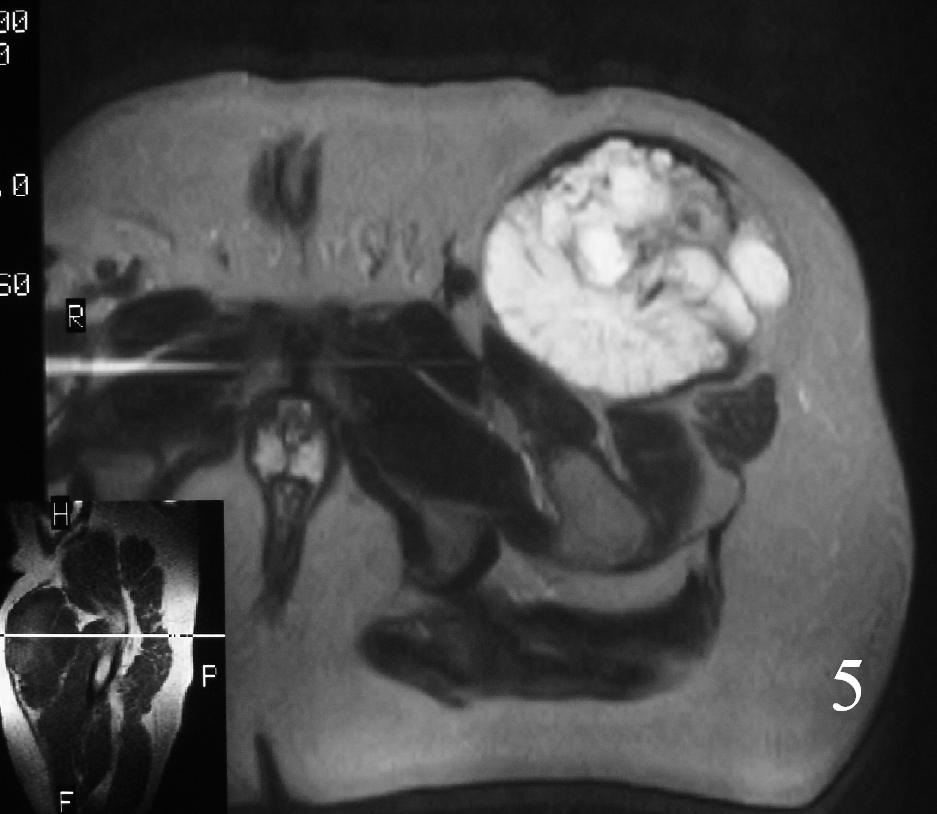

MRI (Fig. 3-7)

• Shows lobulated soft tissue mass

• Signal intensity similar to that of skeletal muscle on T1W

• Heterogenous signal intensity greater than that of fat on T2W

Fig. 3

Fig. 4

Fig. 5

Fig. 6

Fig. 7

Fig. 3-7 Axial MRI of the lower extremity shows an extraskeletal soft tissue chondrosarcoma in different sequences with and without contrast (Fig. 3, 4, 5). Sagittal MRI (Fig. 6, 7) T1 with-without contrast demonstrates enhancement of the mass